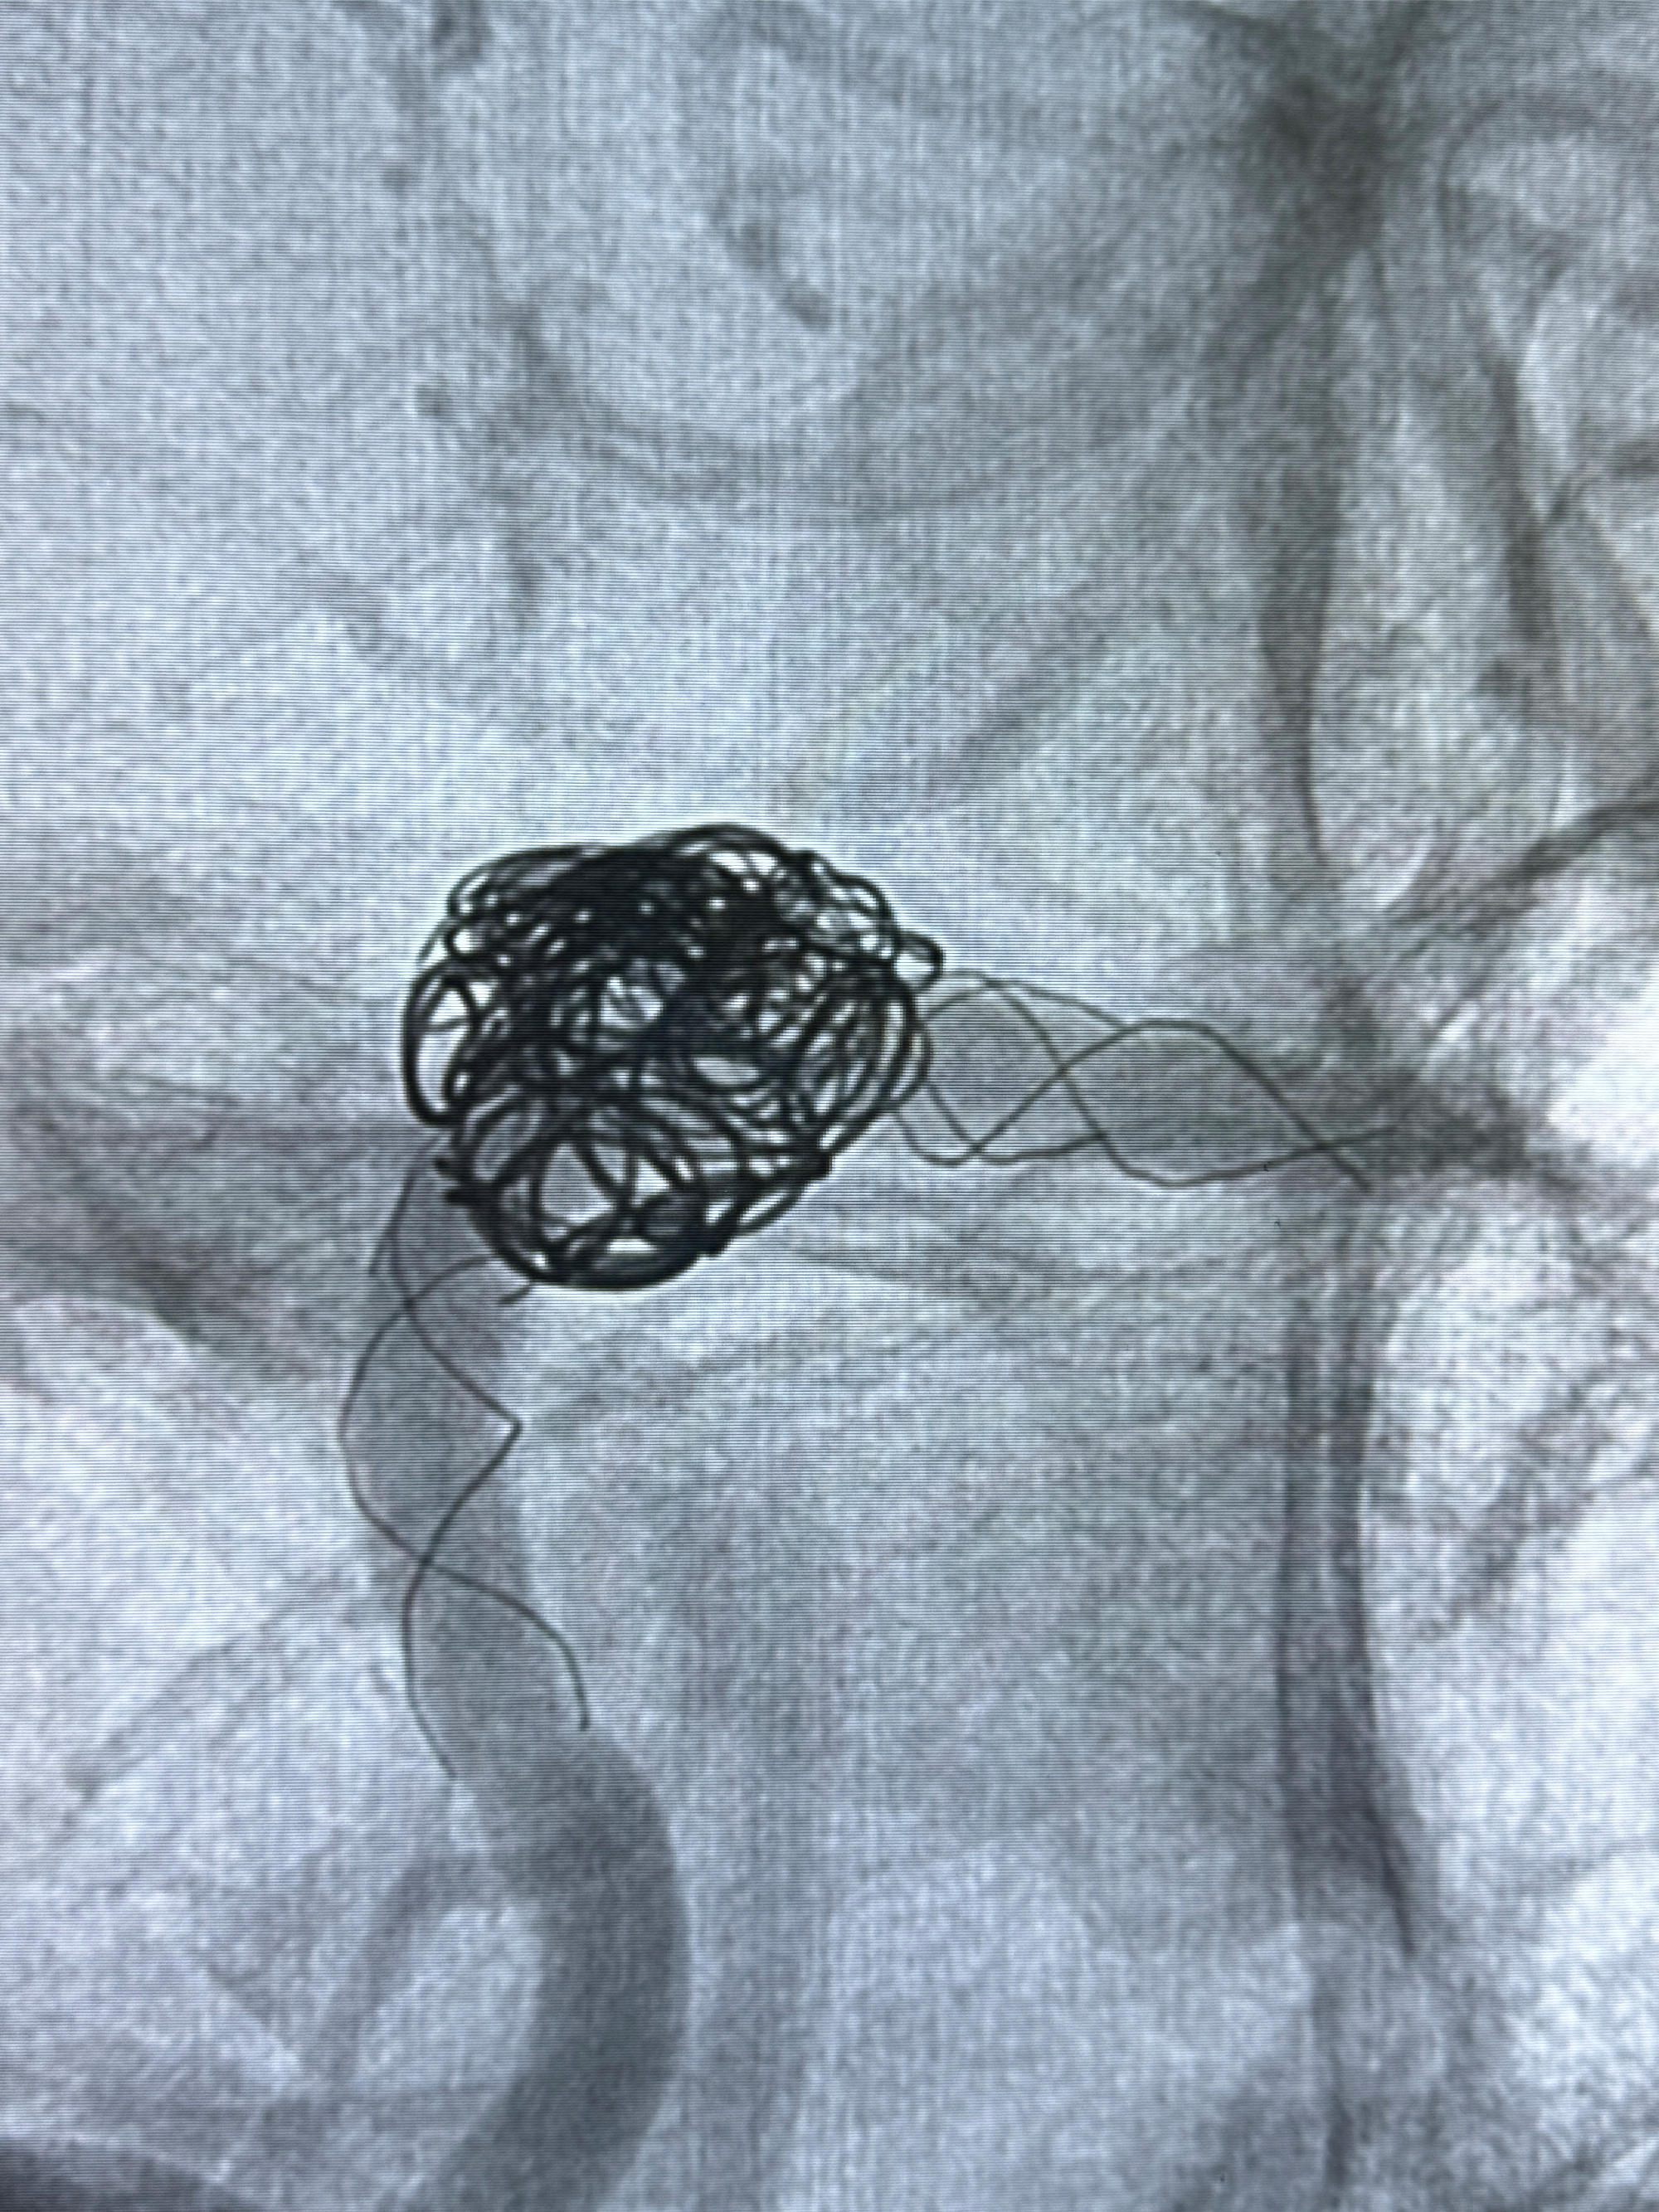

现病史:患者诉2022.06.24因“检查发现颅内动脉瘤”就诊于华山医院查全脑血管造影诊断右侧椎动脉夹层动脉瘤(14.86*12.02mm),随后在全麻下行支架辅助栓塞术(LEO,本人诉2枚支架),术顺,术后予以阿司匹林、氯吡格雷、阿托伐他汀钙片对症治疗;术后3月因下肢淤青停用氯吡格雷,患者近2月开始出现发作性右侧枕部隐痛不适,持续时间约几分钟,着凉可诱发,余一般情况可,目前服用阿司匹林1片qd治疗中,为复查脑血管造影收入我科。

2024-01-08DSA:右侧椎动脉V4段夹层动脉瘤双支架辅助弹簧圈栓塞术后

患者支架辅助治疗后18个月,动脉瘤痊愈